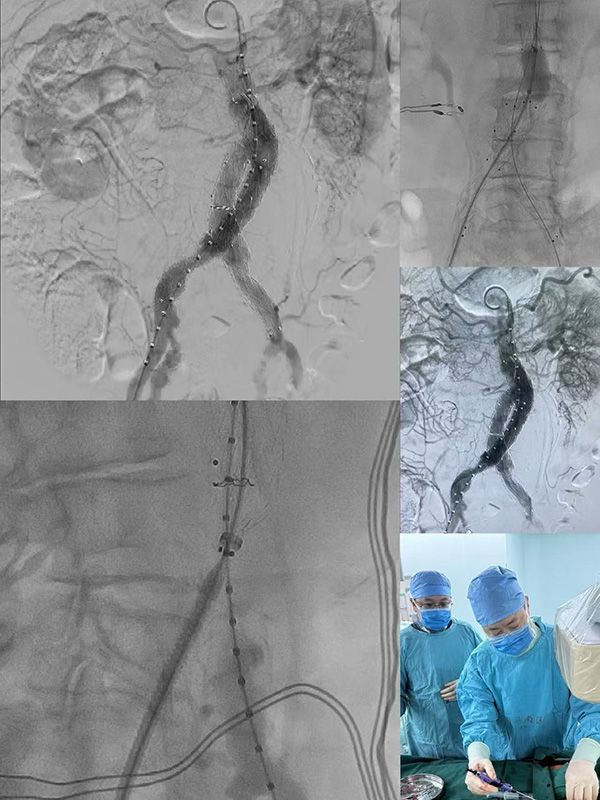

国庆假期,北京同仁同仁医院医护团队坚守手术灯下,成功为挽救了一名巨大腹主动脉瘤患者与的生命。

巨大腹主动脉瘤如同体内的“不定时炸弹”,随时可能破裂引发致命风险,手术容不得半分差错,北京同仁医院血管外科冯亚平教授团队和麻醉科、手术室医护团队术前反复制定手术方案,将术中可能出现的风险点纳入预案。

手术开始,主刀医生凝神专注,在毫米间精准操作,麻醉医师、护士、技师各司其职,默契配合。

一小时后,手术顺利完成。当手术门缓缓打开,医护人员第一时间走向等候的家属:“手术很成功,放心吧!”简单一句话,让内心紧绷的家属瞬间红了眼。